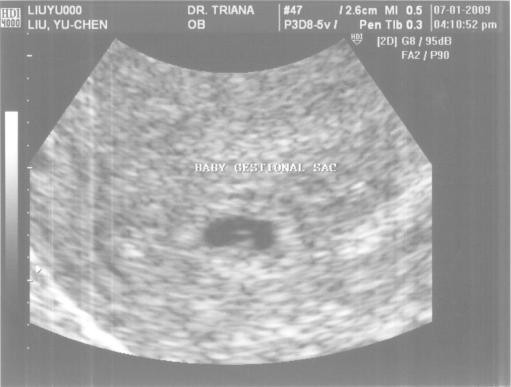

之後還照了超音波,拍了北鼻的第一張照片,不過老實說,那個黑點真的昰北鼻嗎?真是難以相信。也藉由這次超音波,判斷了北鼻年紀為:

5.5-7周。也抽了一堆血,剛開始我還跟護士有說有笑,後來一管一管的空管子不斷被插入接收頭,裝滿之後又換一管,原本噴射出來的血,流速也逐漸緩慢,我這輩子還沒被抽過這麼多血哩!嚇死我了,不過我還是跟護士搞笑說:「待會我自己開車回家沒問題吧?!」哈哈~

小黑點年齡:5.5-7周(還無法說個準)

今天拍攝的超音波照片,中間那個黑黑的,就是胚胎哩!!